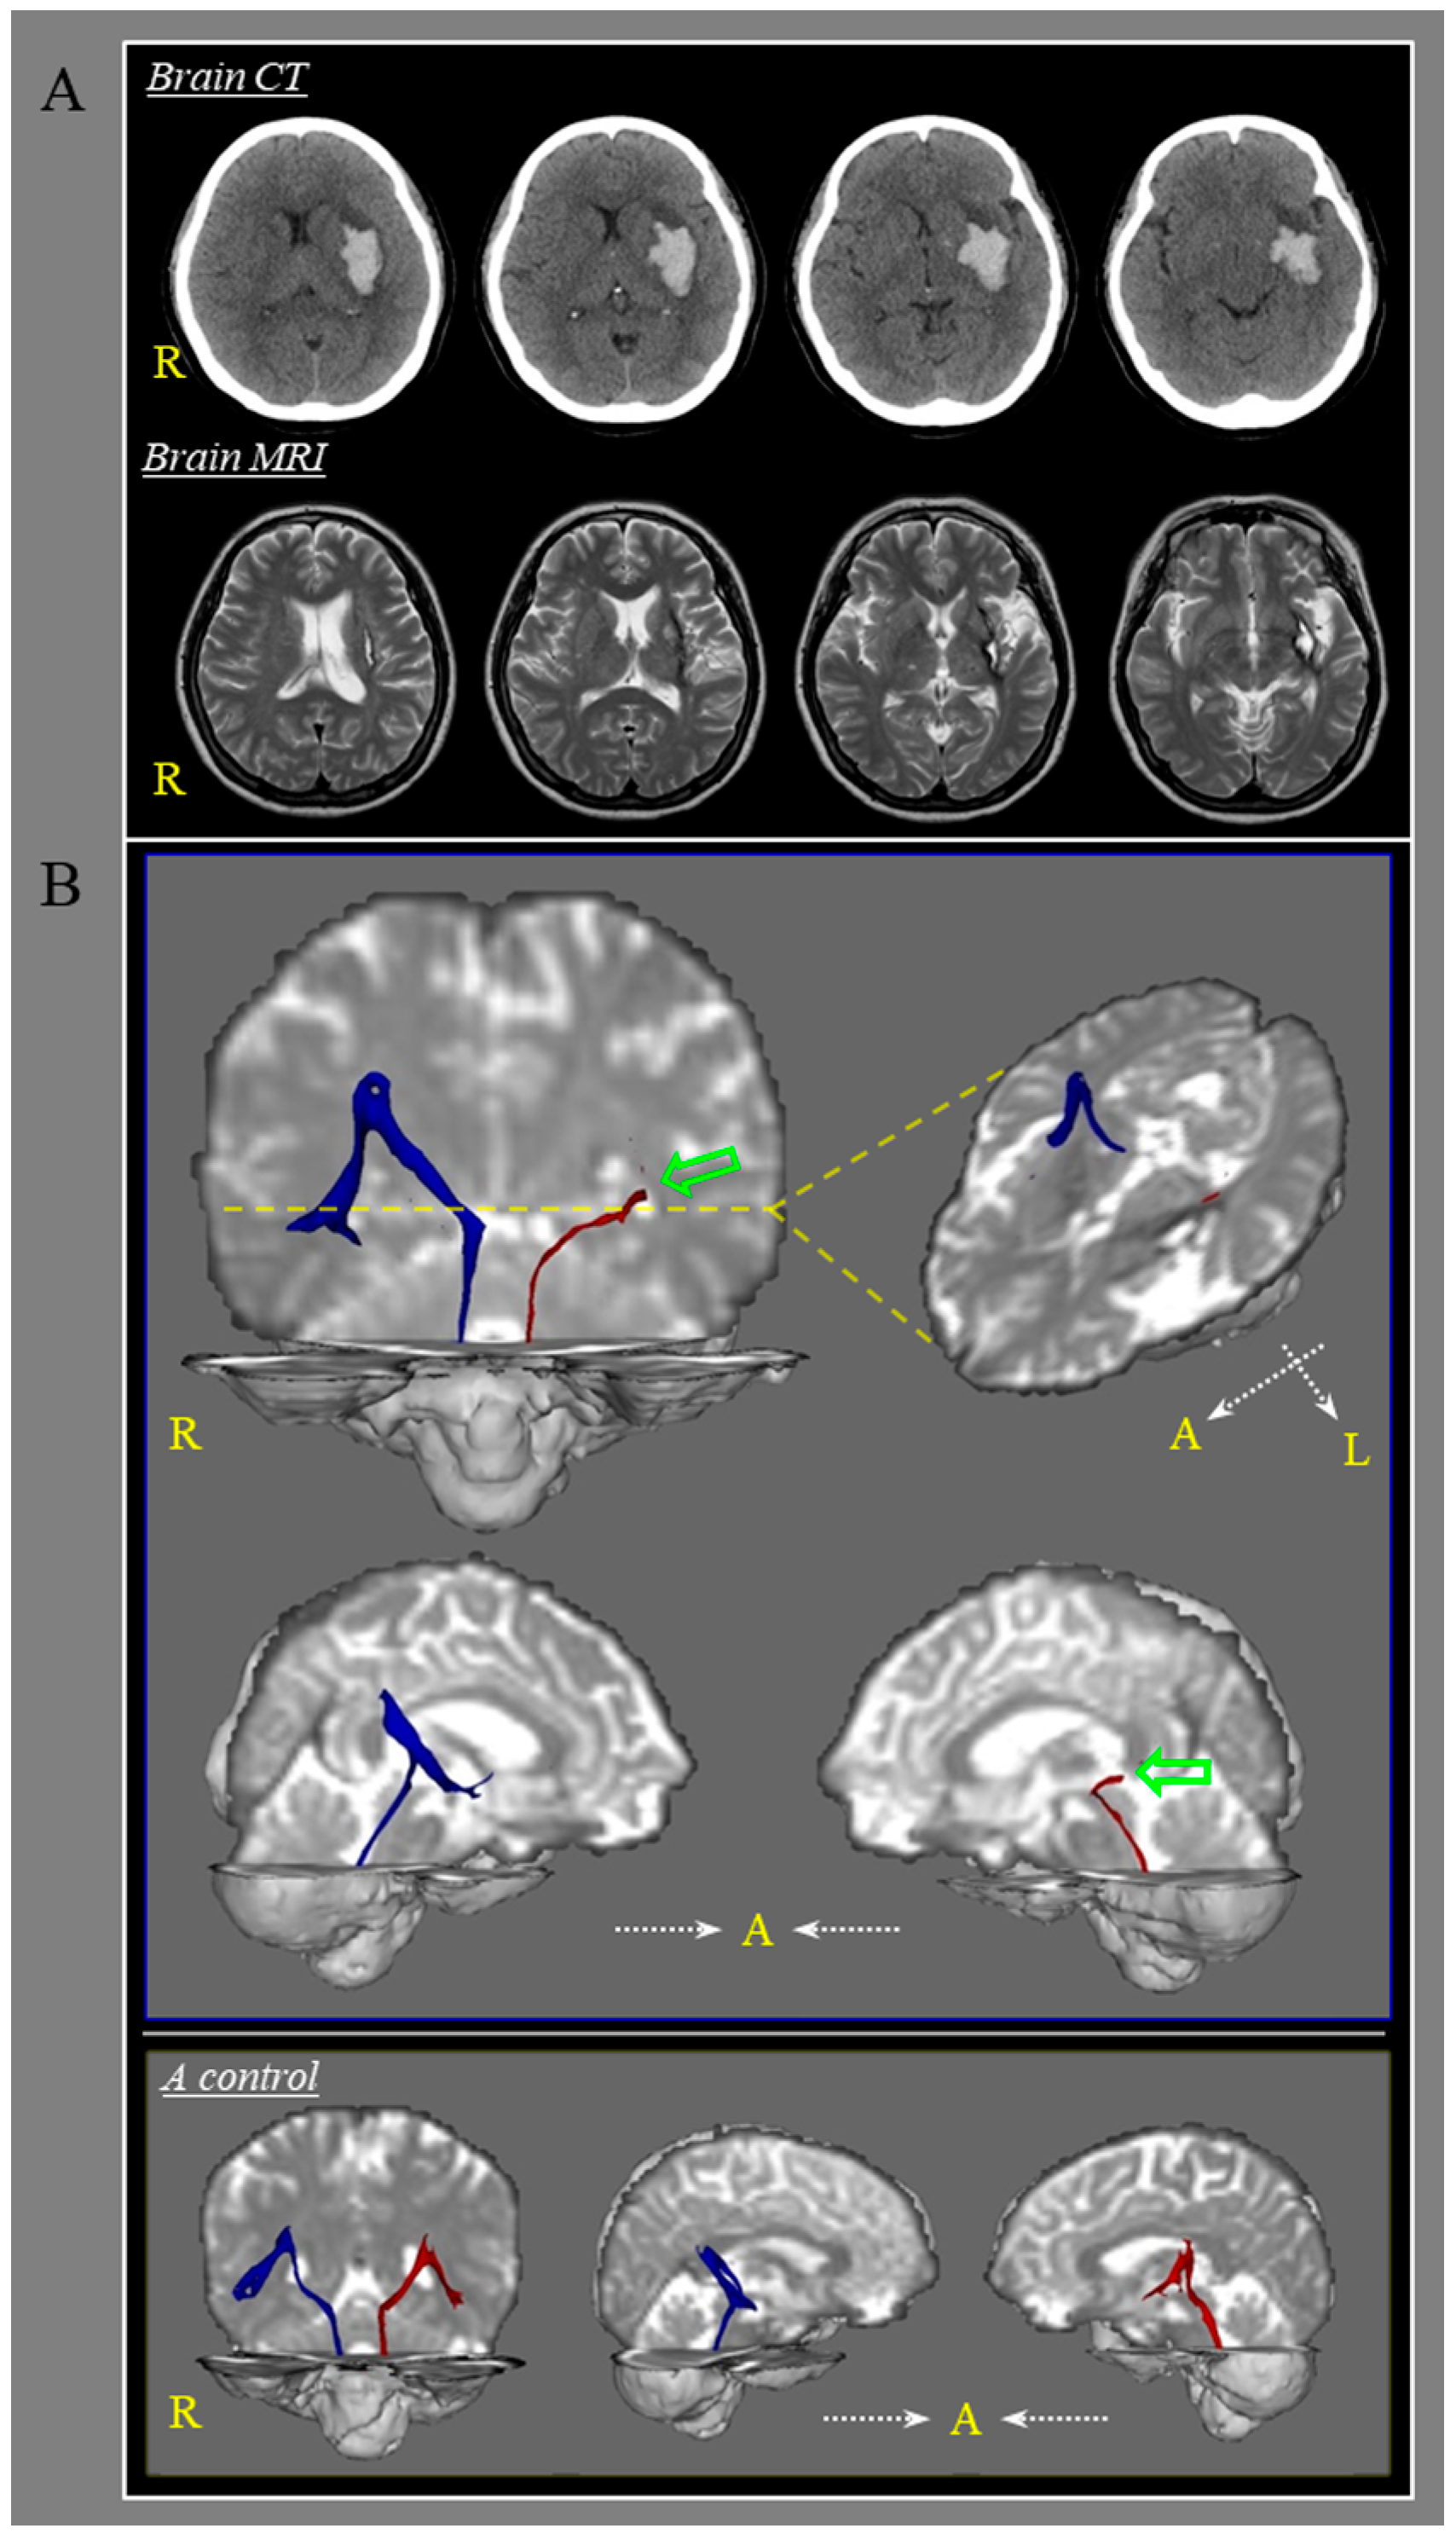

Diagnosis of Dizziness Due to a Core Vestibular Projection Injury in a Patient with Intracerebral Hemorrhage

Kwon, H.G.; Chang, C.H.; Jang, S.H. Diagnosis of Dizziness Due to a Core Vestibular Projection Injury in a Patient with Intracerebral Hemorrhage. Diagnostics 2020, 10, 220. https://doi.org/10.3390/diagnostics10040220